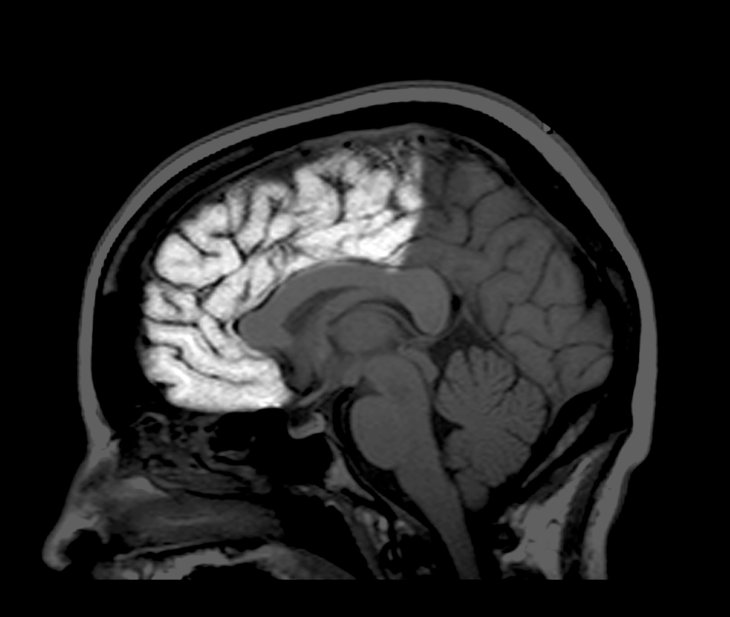

El cerebro humano alcanza su volumen adulto a los 10 años, pero las neuronas que lo componen continúan cambiando durante años después de este hecho. Se van podando conexiones entre neuronas vecinas y se crean nuevos enlaces entre áreas del cerebro que están más alejadas.

Finalmente esta reformación se ralentiza, signo que el cerebro está madurando. Pero esto ocurre a ritmos diferentes y en diferentes partes del cerebro.

Esa poda en el lóbulo occipital, en la parte trasera del cerebro se hace más angosta a los 20 años. En el lóbulo frontal, delante del cerebro, se continúan formando nuevos enlaces a los 30 y más adelante.

A medida que la anatomía del cerebro cambia, también lo hace su actividad. En el cerebro de un@ niñ@, las regiones colindantes tienden a trabajar juntas. En la madurez, regiones más distantes empiezan a concetarse. L@s neurocientífic@s han especulado que esta harmonía a larga distancia permite que el cerebro adulto trabaje más eficientemente y sea capaz de procesar más información.